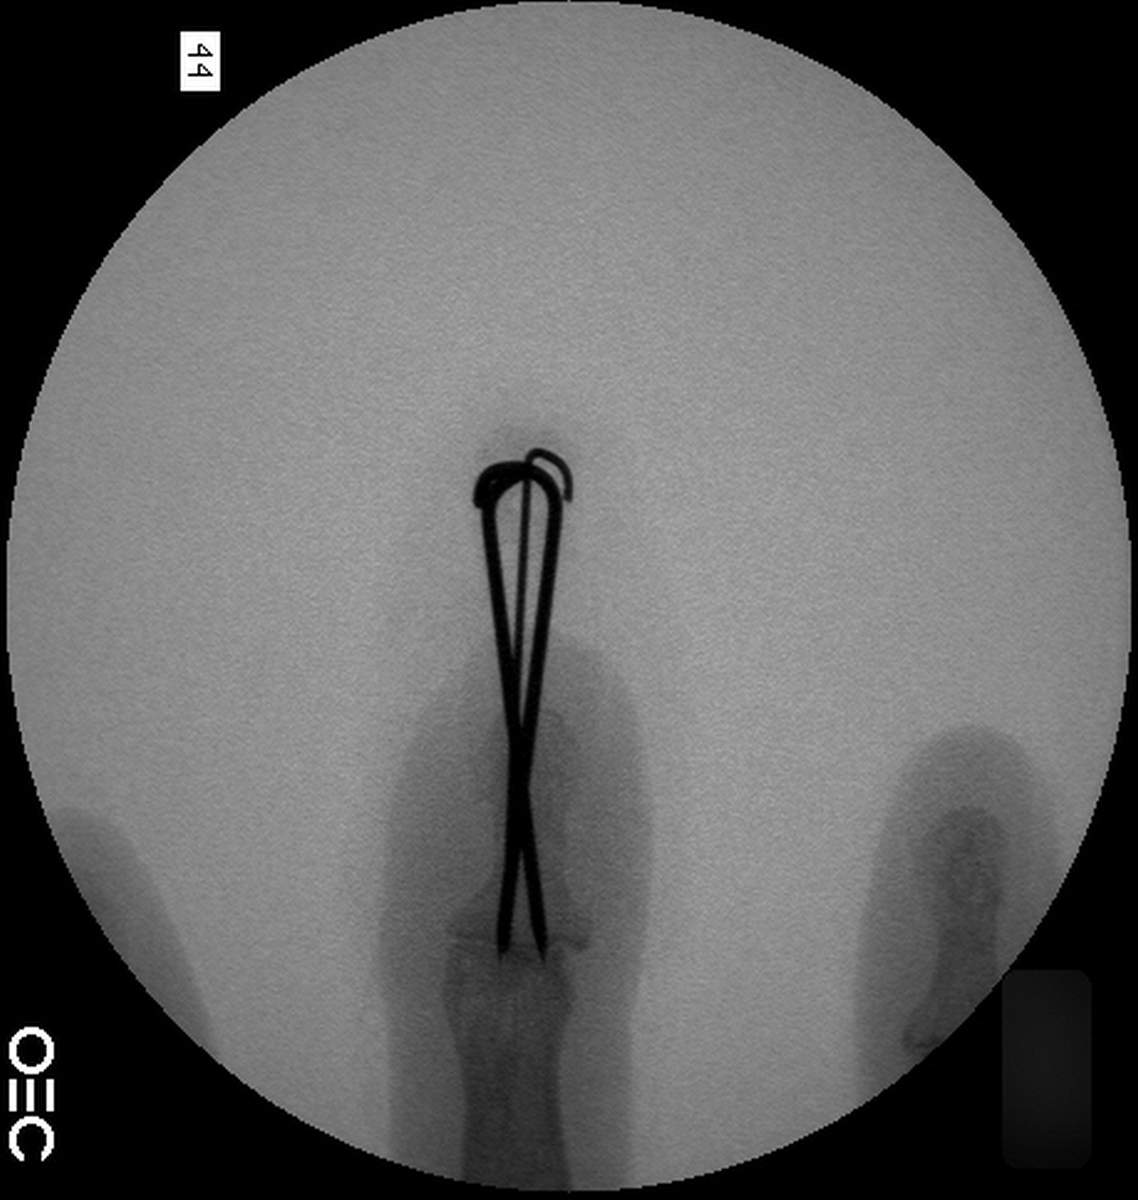

Case 3

Acute mallet fracture treated with percutaneous

pinning: proximal pin stabilizes the fracture

fragment, longitudinal pin maintains distal phalanx

position. |

| Thermoplastic bonding of the protruding ends: appearance at one month. |